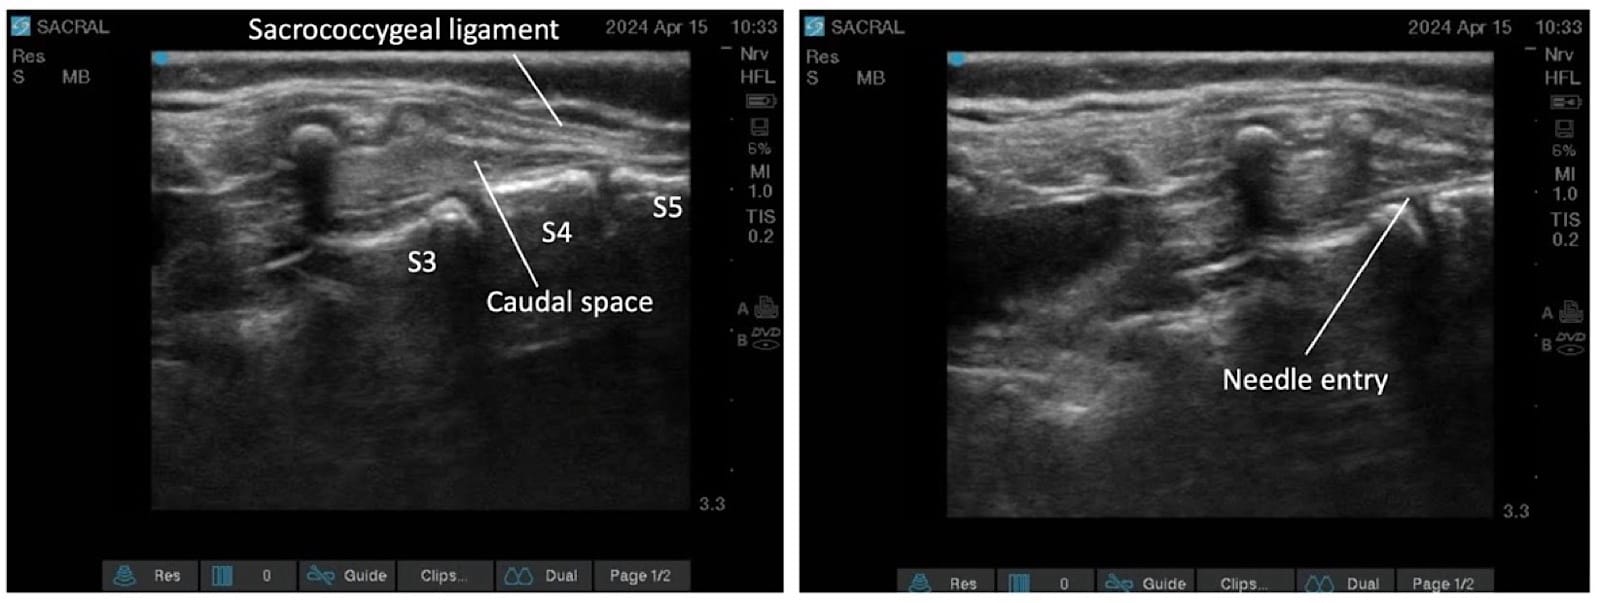

Proper ergonomic positioning is essential, with the ultrasound screen and procedural field aligned along the operator’s natural line of sight. This facilitates precision and reduces operator strain. A high-frequency linear or hockey stick ultrasound transducer is used to optimize visualization of the superficial sacral anatomy. Key structures, including the sacral cornua, the sacrococcygeal ligament, and the caudal canal, should be clearly identified on the ultrasound image. The needle is then advanced in plane under continuous real-time USG to ensure accurate trajectory and safe entry into the caudal space. Alternatively, out-of-plane needle insertion during transverse scanning is an option. Adequate placement is confirmed by cephalad drug spread, dura displacement, and posterior epidural expansion. (Figures 10–15)